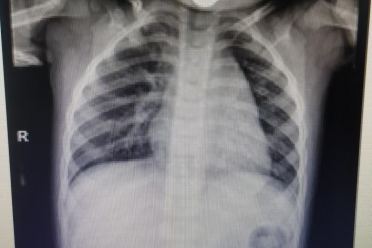

- 6岁女孩“感冒”后,喘不上气,命悬一线…… 2025-09-19 | 儿二科